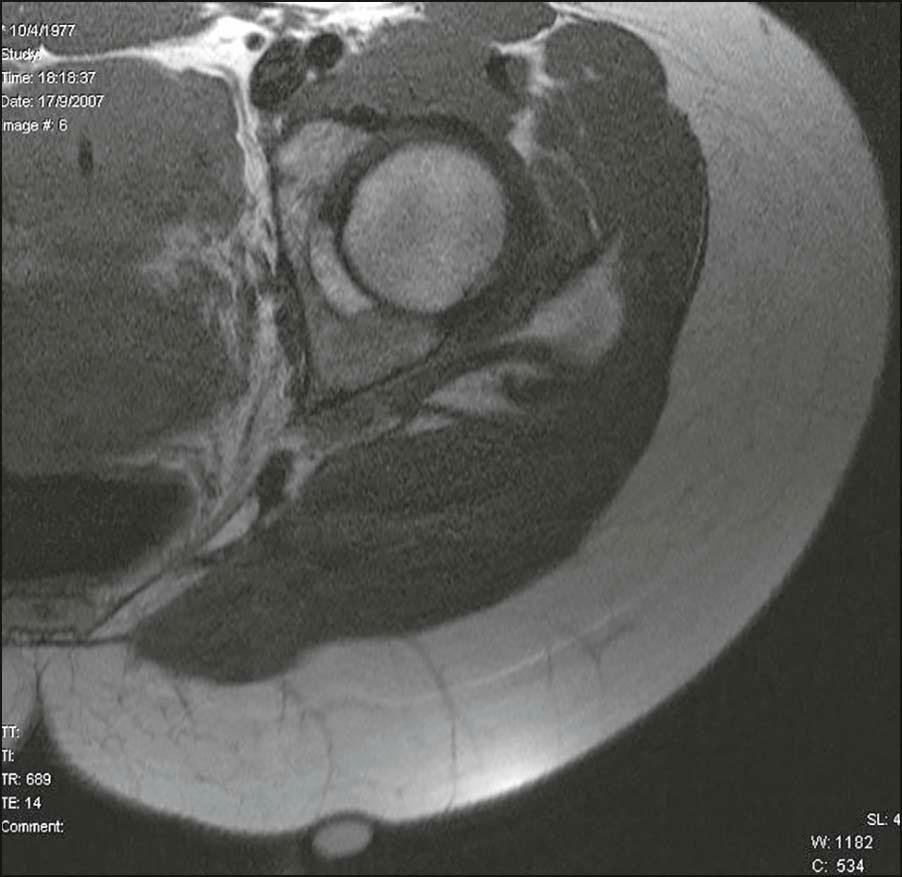

In 2009, a study employing magnetic resonance imaging (MRI) showed the presence of thick subcutaneous septa in about 97% of the depressed lesions typical of cellulite, as evidence of its pathogenesis in this condition. These septa displayed a tree-like morphology. Furthermore, the T2 images also showed the presence of vessels together with the septa ( Fig. 16.1 ).

Figure 16.1, Magnetic resonance imaging of a depressed cellulite lesion with subjacent fibrous septa